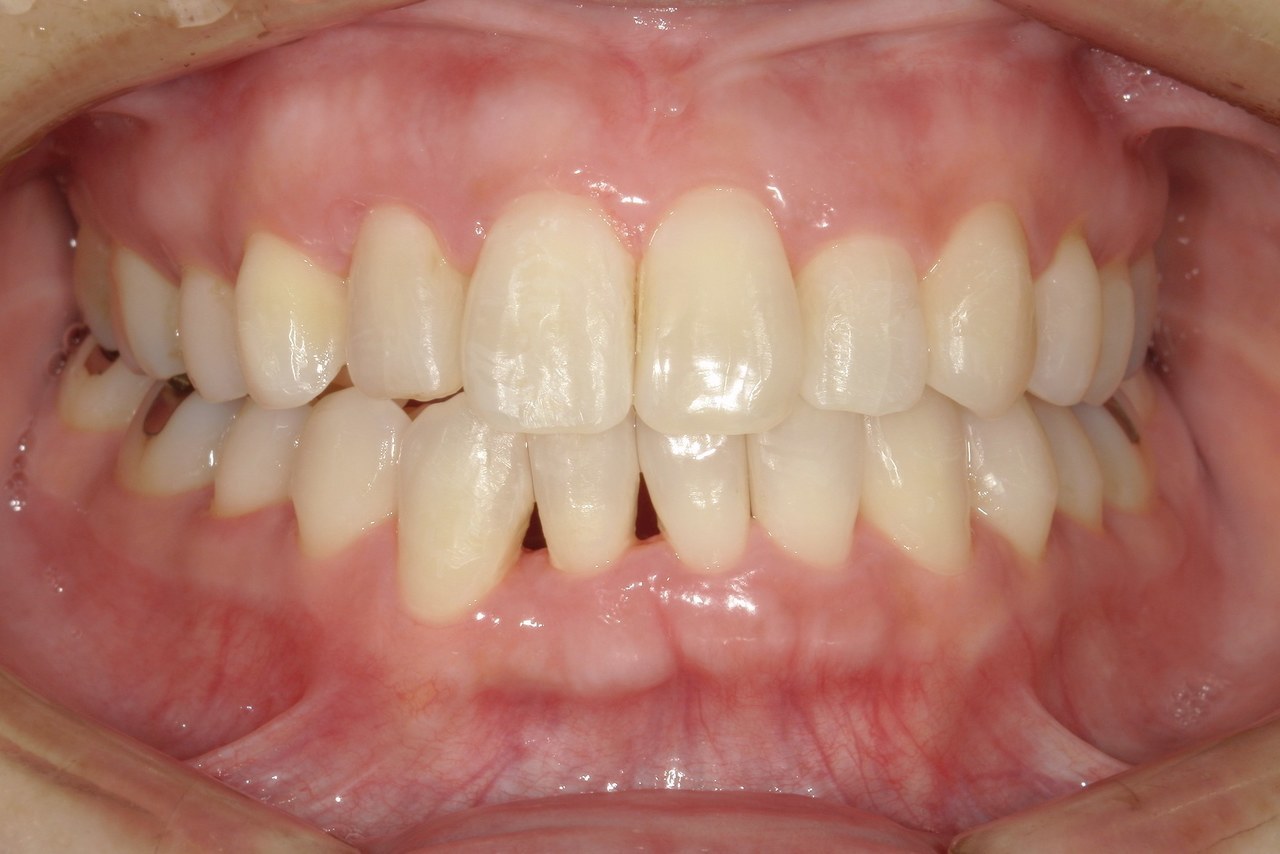

After

浜松市中央区・自動車学校前駅のインビザラインの症例

K.M 20代女性

上の前歯が前方に出ていて横顔が気になるとの主訴でご来院。上下犬歯から犬歯までの6本が噛み合うよう、全体的に歯を内側に移動させることで、前歯の噛み合わせを整え叢生と開咬を治療しました。

​治療の期間:R5. 7/5〜R7. 1/17

​治療の価格:66万円